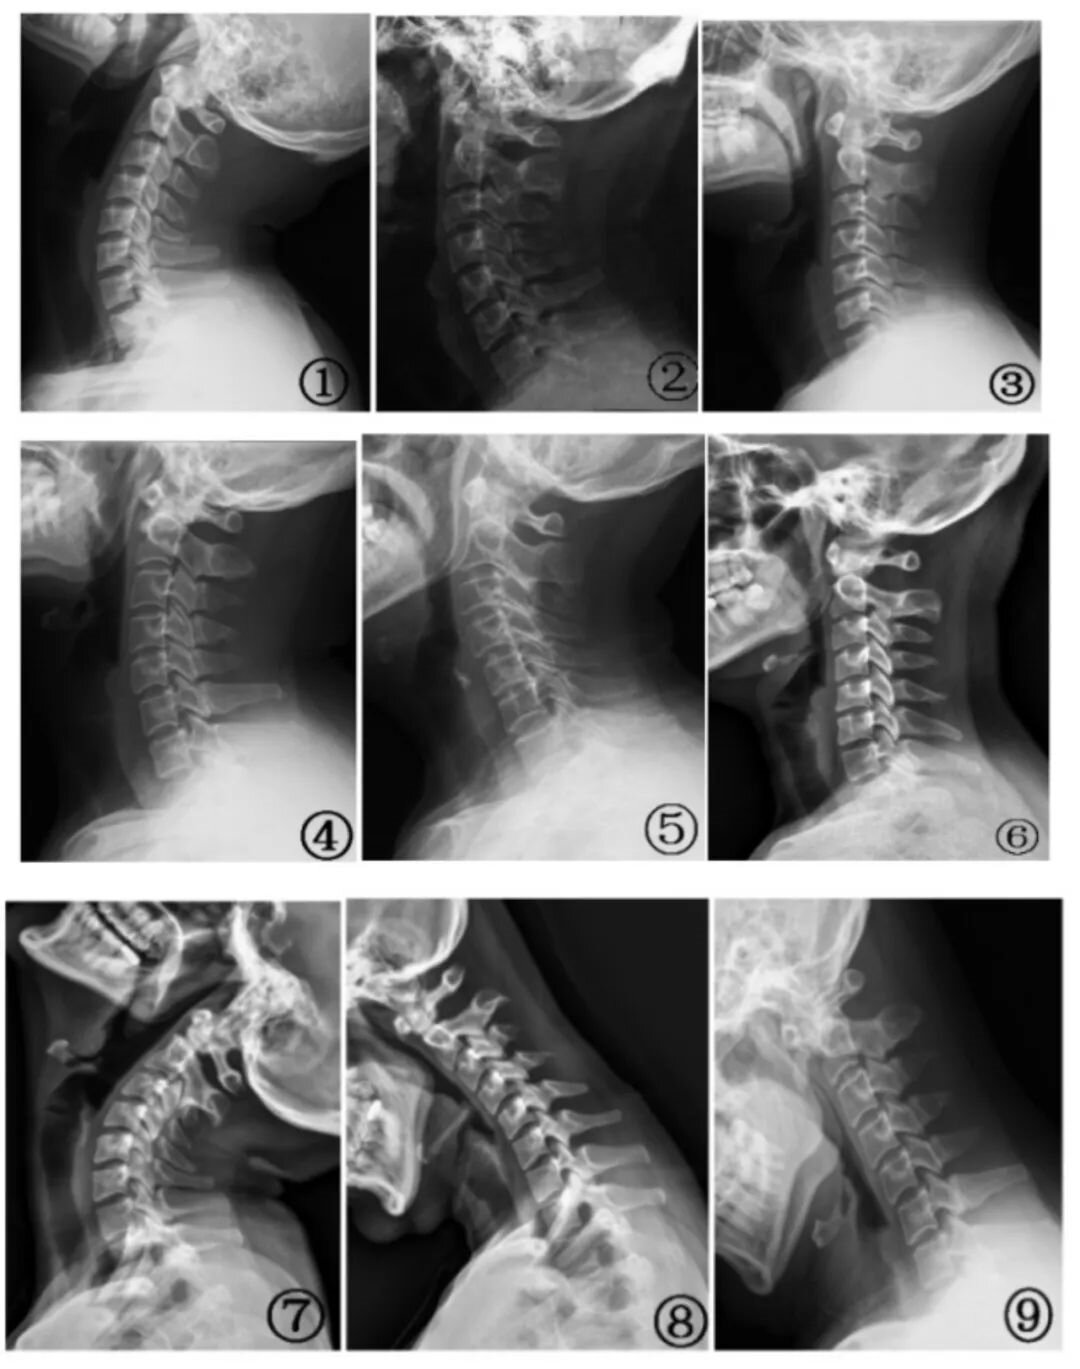

图① 颈椎侧位片;图② 曲度增加;图③ 曲度变直;图④ 曲度变小;图⑤ 弓顶移位;图⑥ 轻度反弓;图⑦ 过伸位颈 4、5 椎体水平位移; 图⑧ 过曲位中段椎体角位移;图⑨ 过曲位中下段椎体角位移和颈 5、6 水平位移。图片来自参考文献[1]